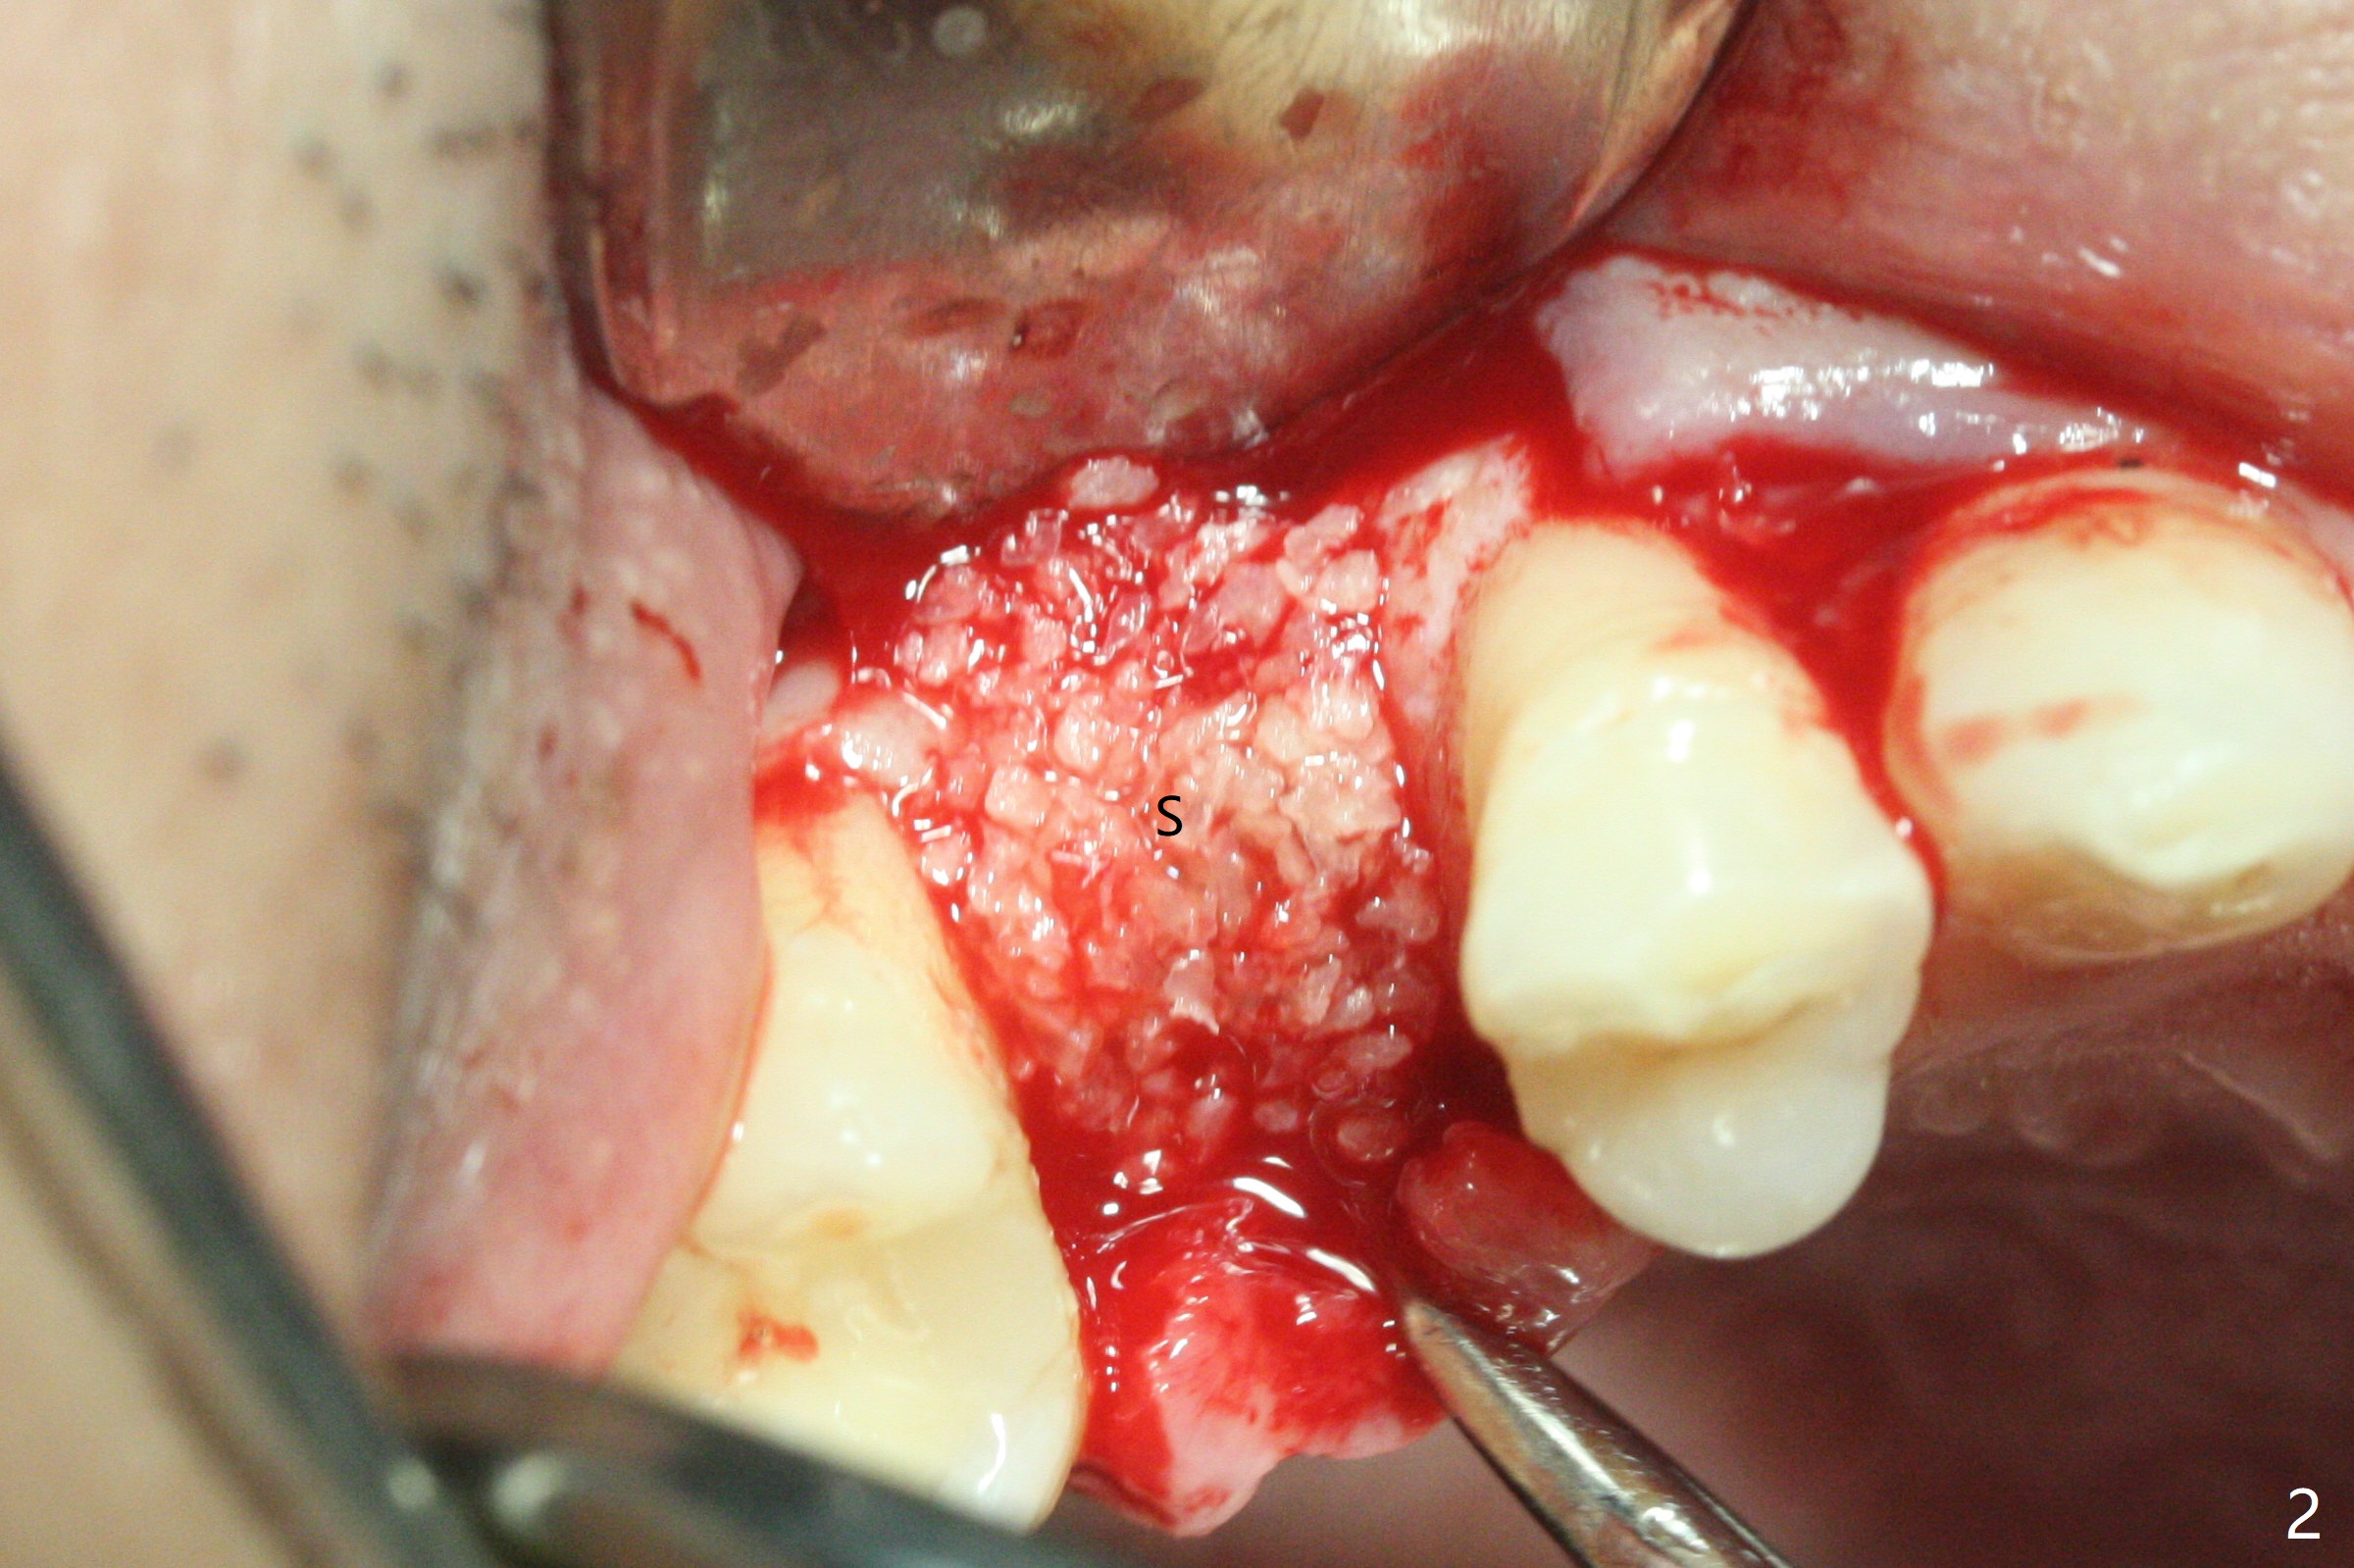

尽管没有任何症状,右上5牙冠粘固后2年5个月,牙冠与基台取出(没有使用扳手,说明基台未完全就位),切开,去除少量肉芽组织,仍然发现植体螺纹暴露(图一),使用一种叫I Brush 钛合金刷子清洁后,放置粘性骨块(图二: S),它坐在牙槽嵴上仿佛非常安稳,多么象马鞍(Saddle)。覆盖一张PRF膜和一小张Cytoplast(不可吸收膜,Osteogenics (company) 图三:箭头),使用PTFE缝线(与Cytoplast同样一种材料)缝合。术后即刻根尖片显示骨粉服服帖帖地坐落在植体和牙槽嵴上(图四:*)。最后覆盖牙周敷料。后者术后十天左右脱落,伤口愈合正常,颊侧瘘道仿佛消失,颊侧骨壁好像不再凹陷了(图五,六)。术后5周,膜已经脱落,缝线撤除后,伤口好像二期愈合,但愿肉芽组织下面骨粉尚未损失太多。术后三个月根尖片显示骨粉减少(图八)。不可吸收膜脱落可能造成骨粉流失。应该做减张缝合。术后4.5个月颊侧骨壁又凹陷(图九:箭头,需要decortication),但是uncover时植体周围都有骨质包绕,术后咬翼片也证明近中,远中骨质接触植体(图十:由于找不到合适愈合基台,直接放置基台和牙冠)。粘固后2.5个月虽然颊侧骨板凹陷,但是没有植体周围炎迹象(图十一)。